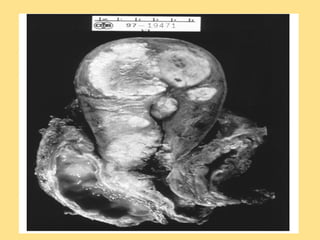

Pathology Gross

Pathology

• figure